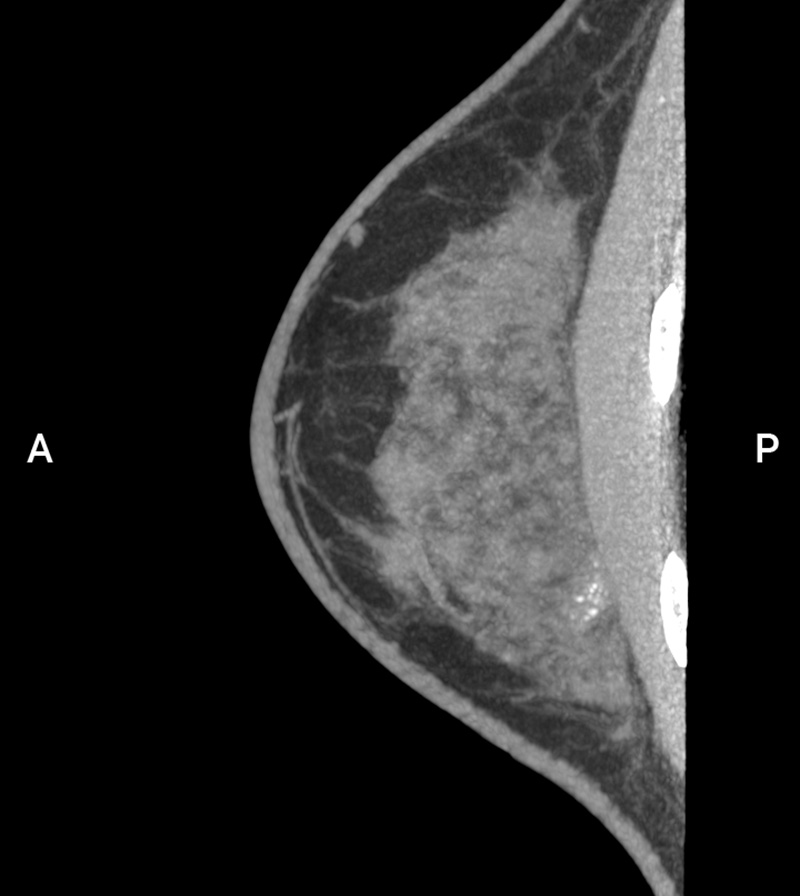

评估: BI-RADS 3

图片来源:Prof: Prof. Dr. med. Andreas Boss (USZ - 苏黎世大学医院)